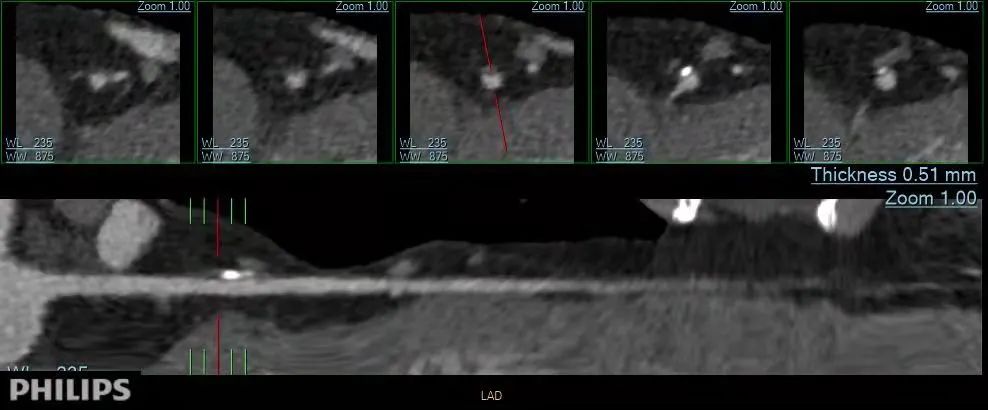

【院内时讯】锦州市妇婴医院放射线科顺利完成院内首例冠状动脉CTA检查

2021年11月24日,锦州市妇婴医院放射线科工作人员在放射线科主任曹焕带领下,由主治医师于福全、技师李一明相互合作,顺利完成院内首例冠状动脉CT血管成像检查,为临床科医生提供了准确的诊断依据,为医院放射科填补了一项技术空白。